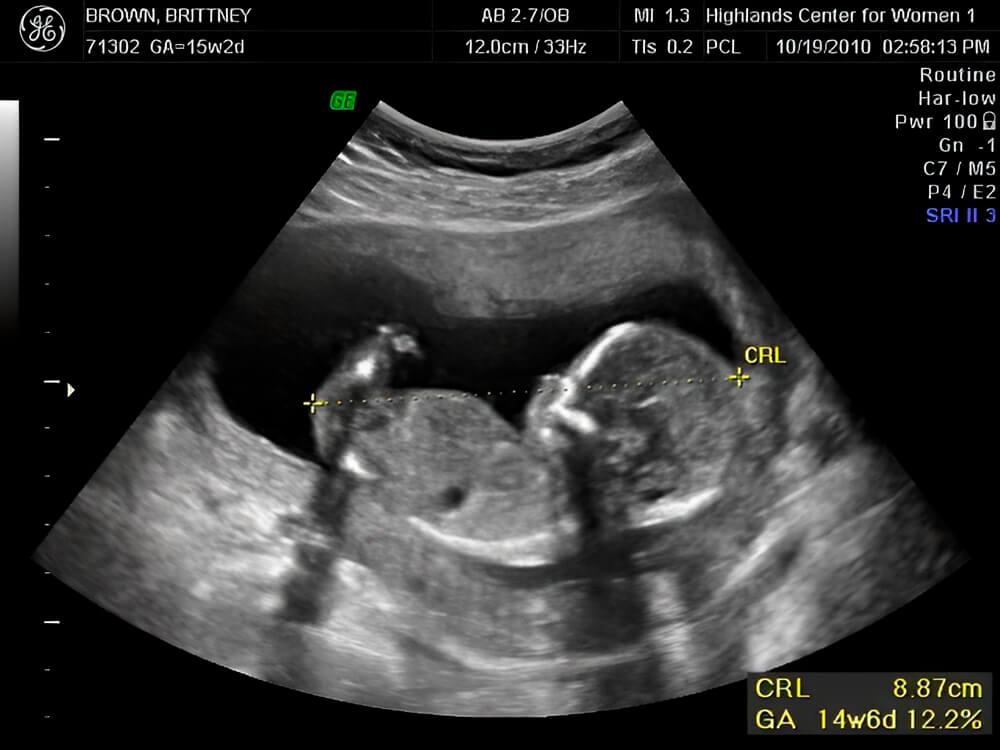

Si estás esperando gemelos

Un ultrasonido puede encontrar que uno de los bebés tiene mayor talla que el otro [2]. Si son dicigóticos (derivados de diferentes óvulos y diferentes espermatozoides), entonces no hay razón para preocuparse. Especialmente si resulta que uno de los bebés es un niño y el otro es una niña (lo que probablemente ya se pueda determinar en este momento) [3]. La diferencia de tamaño se considera completamente normal en estos casos.

Pero si los gemelos son monocigóticos (idénticos) y comparten la misma placenta, los médicos controlarán cuidadosamente si hay un retraso en el crecimiento de uno de los bebés. Para este fin, es posible que tus médicos te pidan que te hagas ecografías más frecuentes [2].